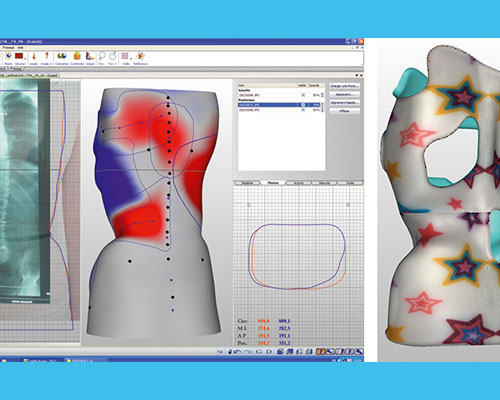

Positif (moulage) :

le moule positif est la reproduction originale du tronc du patient en 3D. Le positif sert pour le thermoformage de l’orthèse.